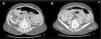

We report the case of a 66-year-old woman with no relevant medical history who presented to the Emergency Department with diffuse abdominal pain of 12-h duration, more intense in the right lower quadrant, accompanied by nausea and vomiting, without constipation or fever. She had a good general condition, with haemodynamic stability and a discreetly distended, tympanic abdomen without signs of peritonitis and decreased bowel sounds. In the blood sample leukocytosis was not observed (leukocytes 9.7×103/μl) and the other parameters were normal (haemoglobin 14.9g/dl, platelets 234×103/μl), except for a CRP of 15.1 and a pH of 7.529. An abdominal CT was performed, which showed distension of small bowel loops with faecaloid content, a significant amount of free liquid, and an image of swirling loops of small bowel lateral to the right colon with stretching of the mesenteric vessels which was consistent with the diagnosis of an internal hernia with signs of intestinal obstruction (Fig. 1).